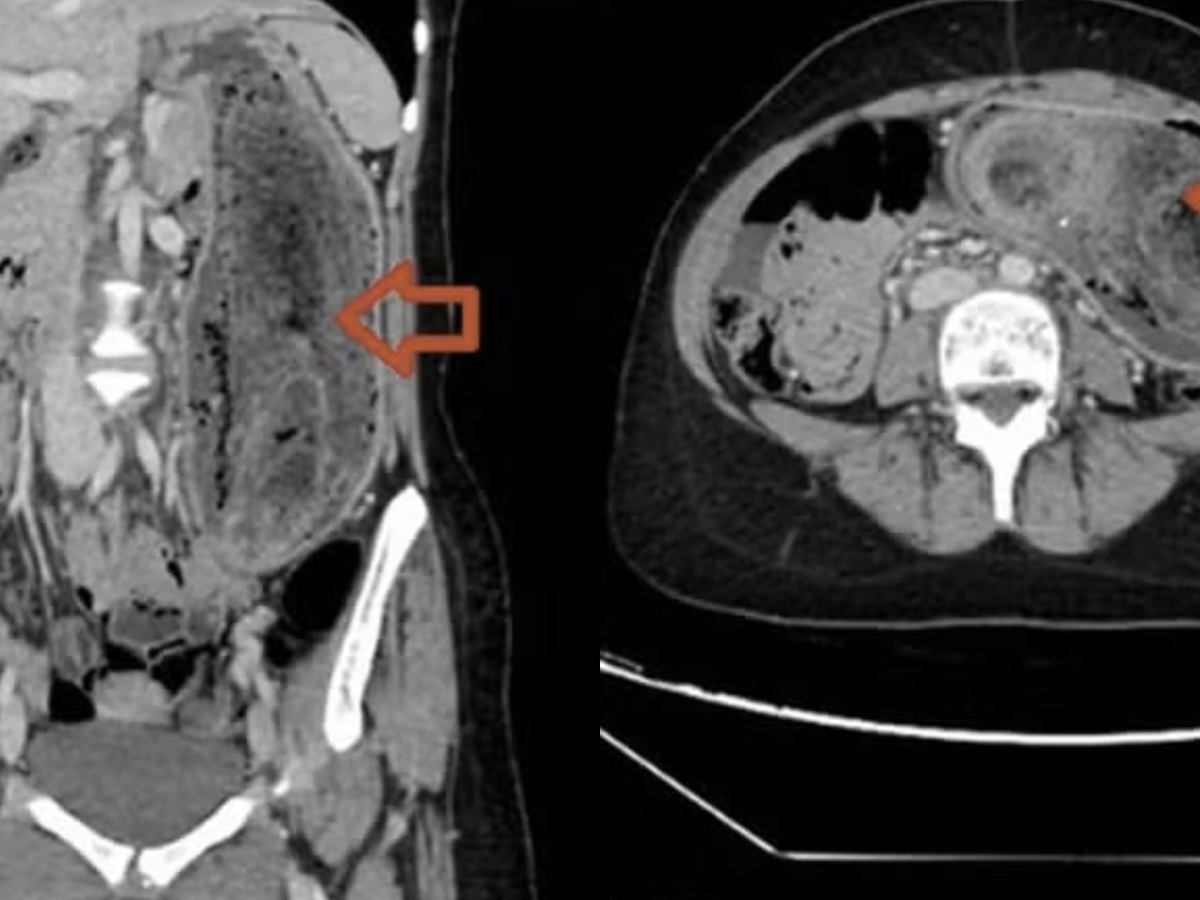

Na avaliação física, os médicos perceberam que o abdômen estava distendido, doloroso e com uma massa endurecida perceptível ao toque. Exames de imagem confirmaram a suspeita: havia um aglomerado de cabelo tão grande que ocupava completamente o estômago e chegava até o duodeno, configurando um quadro típico da "síndrome de Rapunzel".